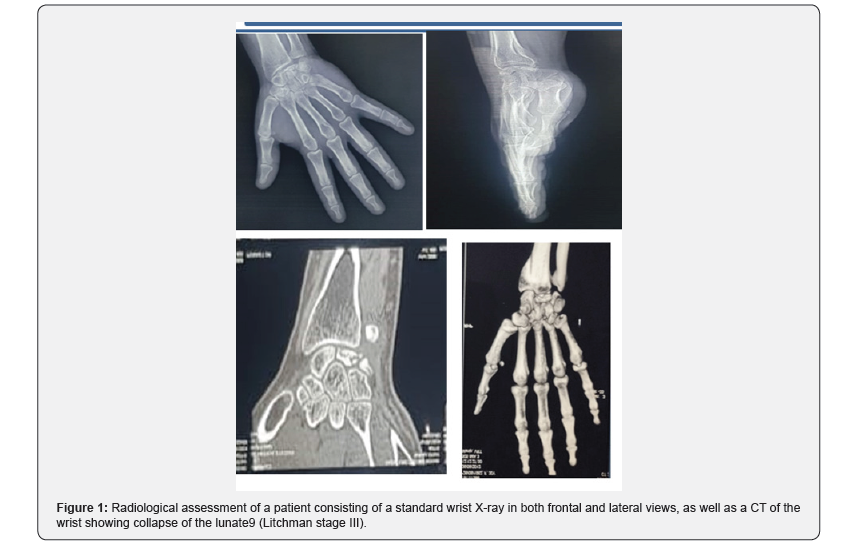

A radiological assessment consisting of a conventional wrist X-ray in both frontal and lateral views, as well as CT, was performed on all patients, allowing for classification of the patients at stage III and IV of Lichtman (Figure 1). All patients underwent the same surgical technique through a posterior approach. The procedure involved opening the retinaculum and denervation of the NIP (nervus interosseus profundus). A T-shaped arthrotomy was performed, followed by resection using a cold blade while preserving the anterior capsuloligamentous plane (Figure 2). Pain significantly decreased in all patients. The VAS score decreased from an average of 6.5 ± 1.2 before the procedure to 2.3 ± 1.1 at the last follow-up (p < 0.01). This pain reduction was consistently observed throughout the follow-up period. Range of motion (flexion/extension) also showed notable improvement. The average flexion/extension increased from 65° ± 10° preoperatively to 85° ± 8° postoperatively (p = 0.02). This improvement allowed the patients to regain satisfactory functional mobility (Figures 3 & 4). Grip strength significantly improved. It increased from 55% ± 8% of the strength of the healthy side to 72% ± 6% at the last follow-up (p = 0.03). The functional wrist score (DASH) decreased, reflecting an improvement in quality of life. The average score dropped from 32 ± 7 preoperatively to 14 ± 5 postoperatively (p < 0.01). No major complications were reported during the follow-up. One patient developed mild carpal osteoarthritis at 4 years postoperatively, but this did not require further intervention.